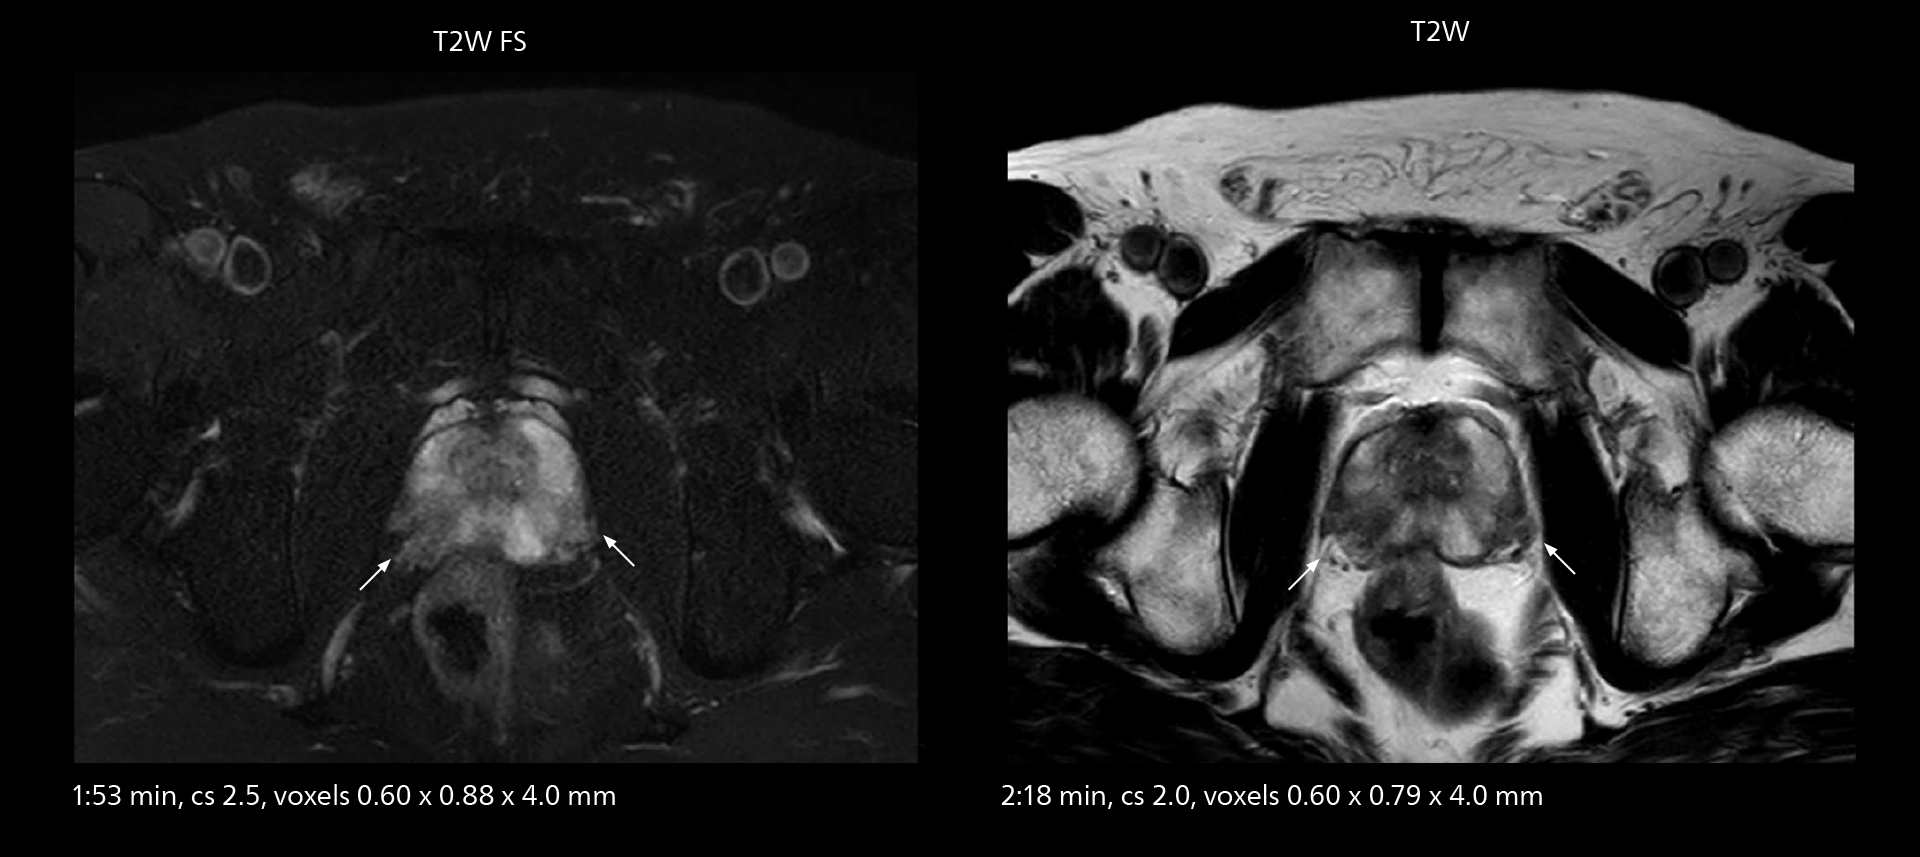

MRI of prostate

Examples of prostate imaging showing faster scan times and improved resolution illustrate the power of SmartPath to Elition X in this case of prostate cancer with PI-RADS score 4.